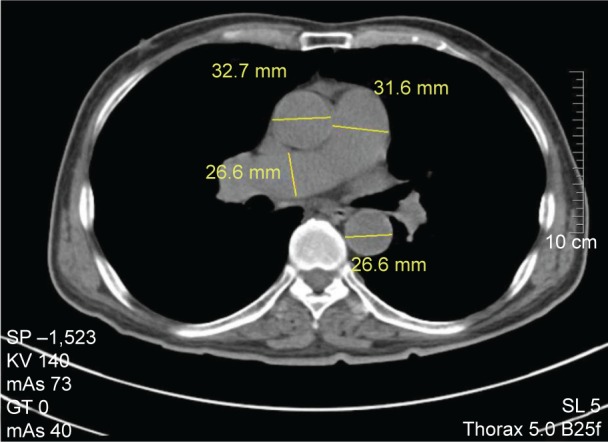

Computed tomography (CT) is widely used for evaluation of lung diseases. To evaluate the value of CT measurement of pulmonary artery for diagnosis of chronic obstructive pulmonary disease (COPD) and its comorbidity pulmonary hypertension (PH), we retrospectively reviewed the CT of 221 patients with COPD and 115 control patients without cardiovascular or lung disease. Patients with COPD were divided into PH (COPD-PH) and non-PH according to systolic pulmonary artery pressure. Main pulmonary artery (MPA), right pulmonary artery (RPA) and left pulmonary artery branches, and ascending aorta (AAo) and descending aorta (DAo) diameters were measured. Meanwhile, the ratios of MPA/AAo and MPA/DAo were calculated. MPA, RPA, and left pulmonary artery diameters were significantly larger in COPD than those in the controls, and this augment was more obvious in COPD-PH. AAo and DAo diameters did not vary obviously between groups, while MPA/AAo and MAP/DAo increased significantly in COPD and PH. MPA could be helpful for COPD diagnosis (MPA diameter ≥27.5 mm, sensitivity 54%, and specificity 80%), and RPA could be applied for COPD-PH diagnosis (RPA diameter ≥23.4 mm, sensitivity 67%, and specificity 76%). There was a marked correlation between MPA/DAo and systolic pulmonary artery pressure (r=0.594, P<0.001). Therefore, chest CT could be a simple and effective modality for diagnostic evaluation of COPD and its comorbidity, PH.

Abstract Image